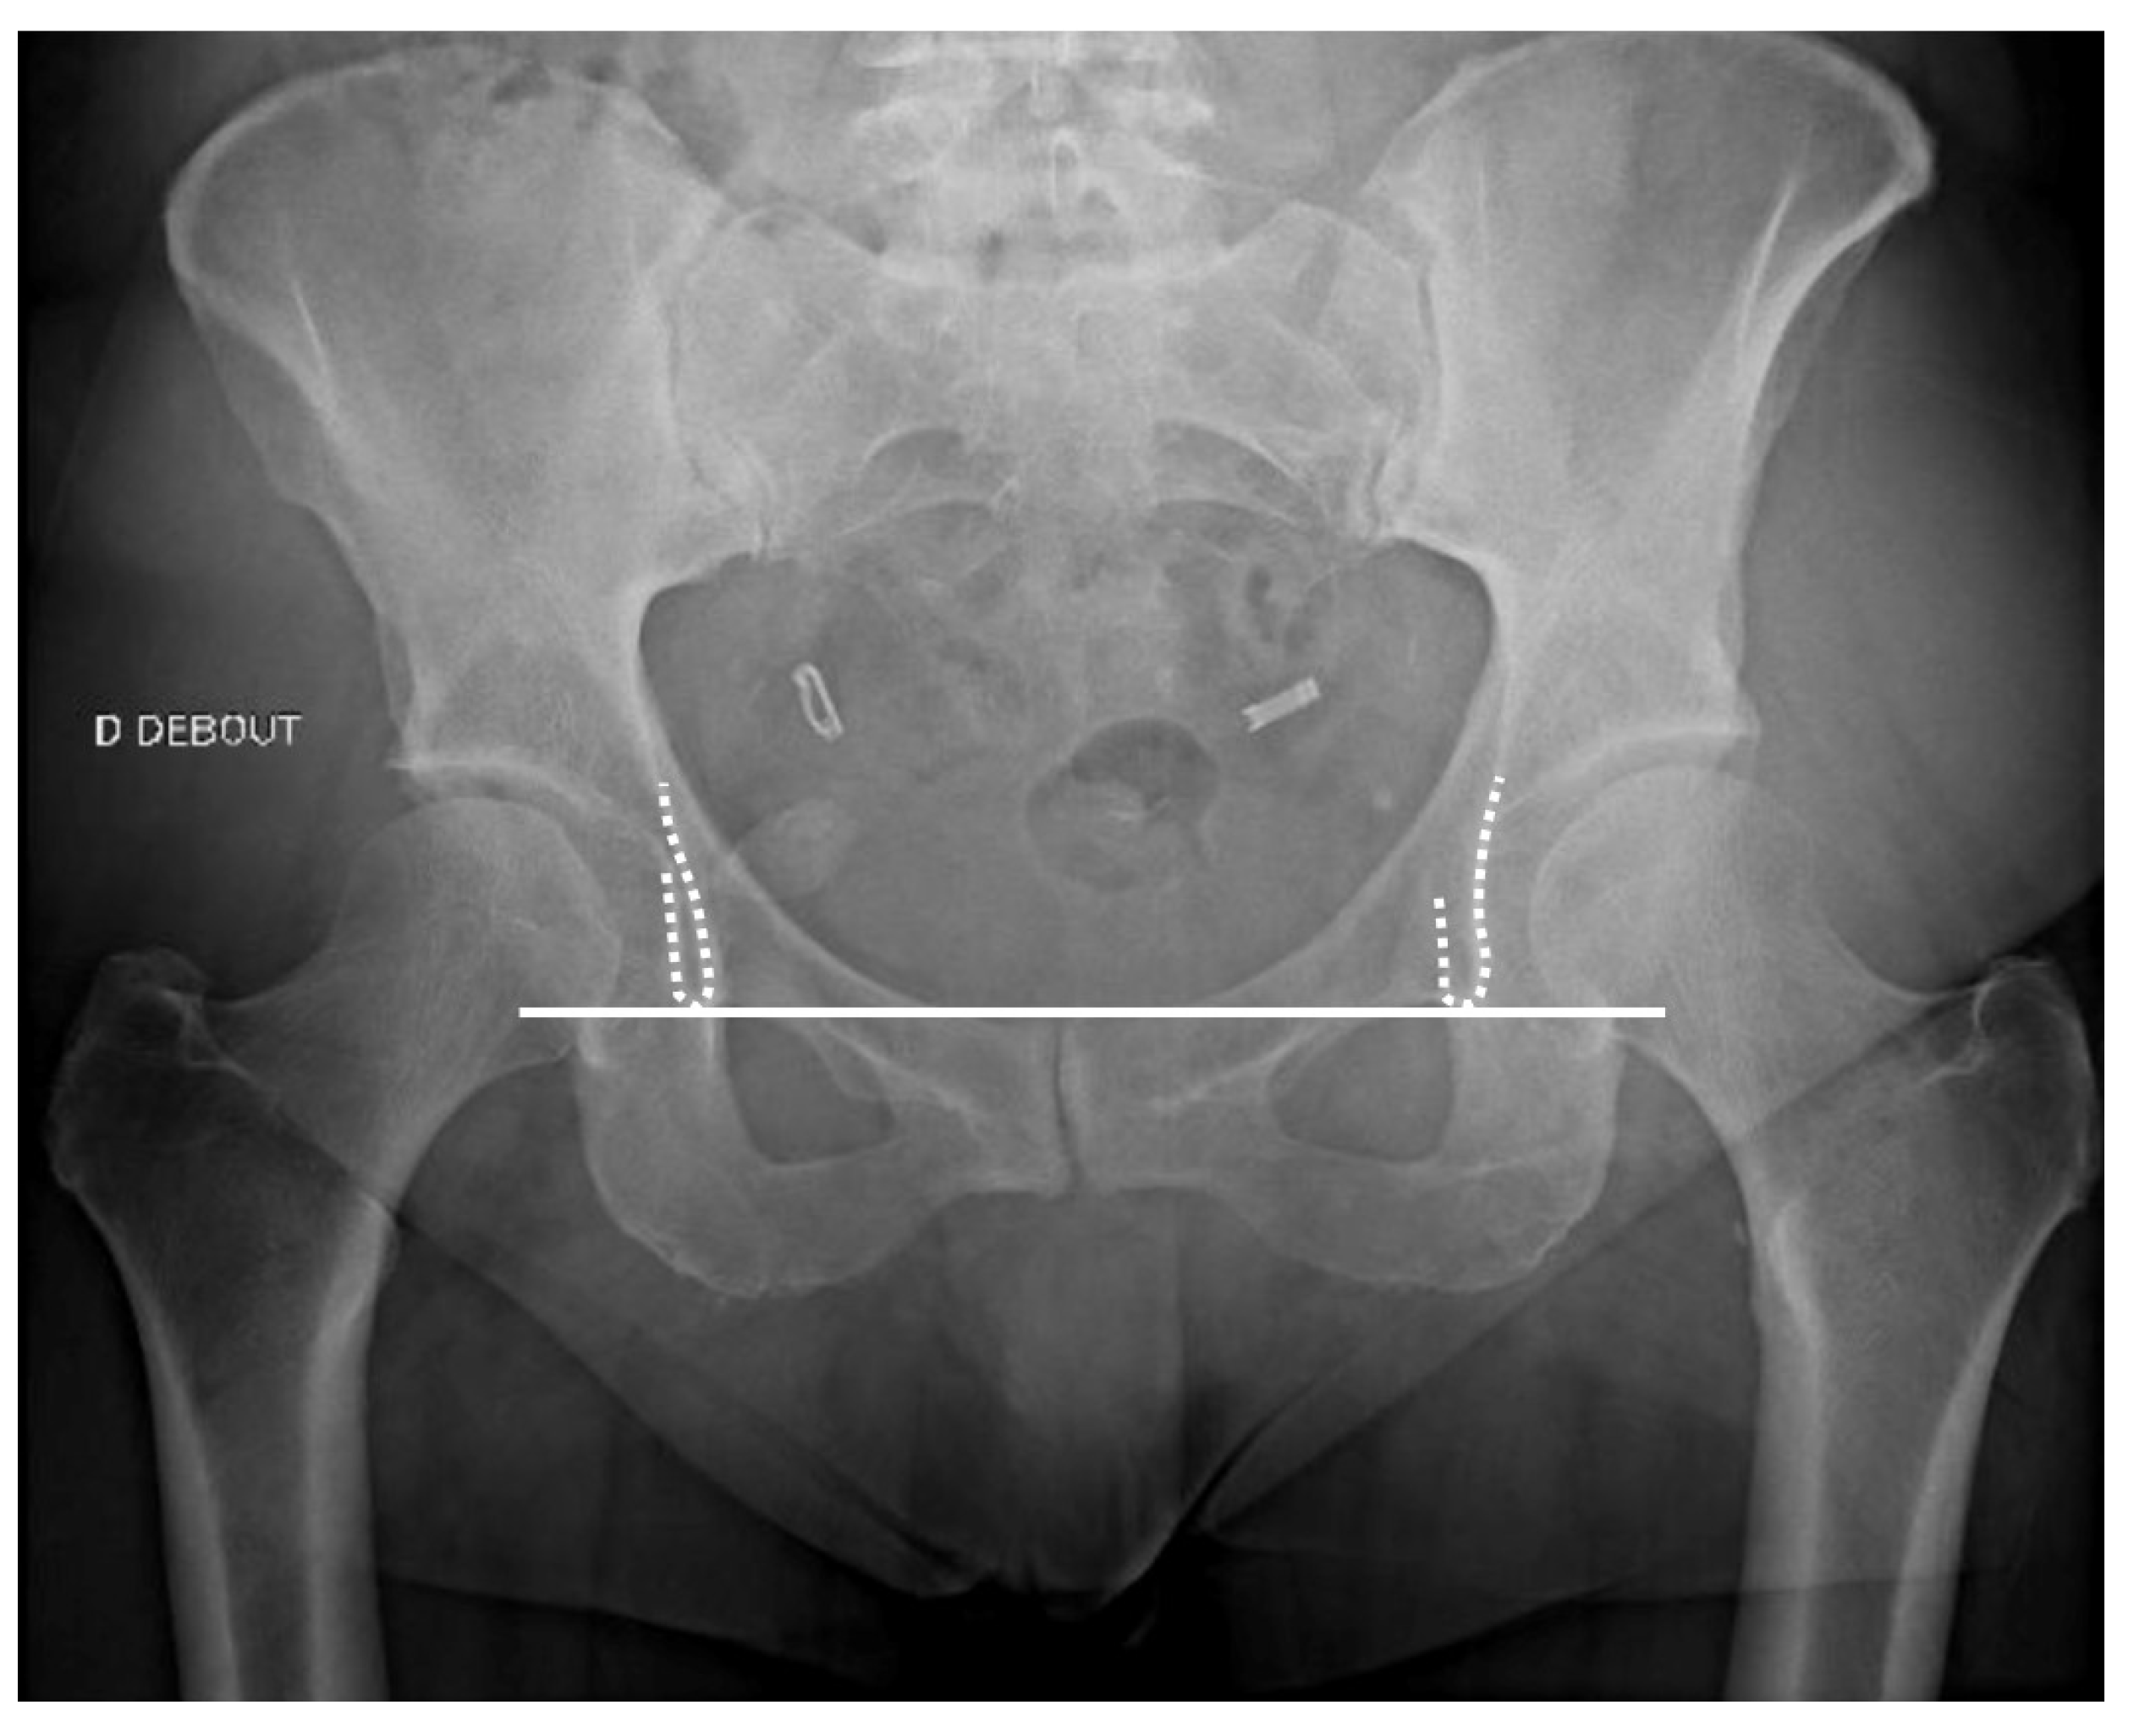

2.3.1. Radiographs Technical Aspects

| Pelvic axis (teardrop sign) | Limb length discrepancy |